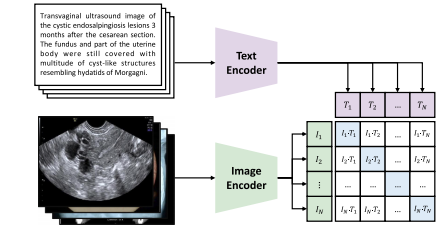

2.1. Contrastive language-image pre-training

CLIP (Contrastive Language-Image Pre-training) is a pre-trainingmethod developed by OpenAI, designed to bridge the gap betweenimages and texts. It jointly optimizes a vision encoder and a textencoder, ensuring that image–text pairs are closely aligned in a sharedlatent space. Unlike other methods that rely on extensive manual supervision or complex structures, CLIP follows the principle of Occam’sRazor (Blumer et al., 1987), favoring simplicity for effective results.Architecture.In terms of its architecture, CLIP seamlessly integrates a vision model with a language model. The visual componentcan be based on either ResNet (He et al., 2016) or Vision Transformer(ViT) (Dosovitskiy et al., 2020), while the language encoder is rooted ina transformer-based model like BERT (Kenton and Toutanova, 2019).As illustrated in Fig. 3, it receives a batch of images and their corresponding text descriptions as input in each iteration. Following theencoding process, the embeddings are normalized and mapped to ajoint image–text latent space. That is, the input images and texts areencoded into 𝐼 ∈ R𝑁×𝐷 and 𝑇 ∈ R𝑁×𝐷, respectively, where 𝑁 denotesbatch size and 𝐷 represents embedding dimensionality.

近年来,与对比语言-图像预训练模型(CLIP)相关的研究发展迅速。在本节中,我们将简要概述CLIP,包括它的通用性以及多种变体。此外,我们还将总结可供CLIP使用的公开的医学图像-文本对数据集。 ### 2.1 对比语言-图像预训练 CLIP(对比语言-图像预训练)是由OpenAI开发的一种预训练方法,旨在弥合图像和文本之间的差距。它联合优化一个视觉编码器和一个文本编码器,确保图像-文本对在共享的潜在空间中紧密对齐。与其他依赖大量人工监督或复杂结构的方法不同,CLIP遵循奥卡姆剃刀原则(布鲁默等人,1987),倾向于通过简洁的方式获得有效的结果。 架构:就其架构而言,CLIP将视觉模型与语言模型无缝集成。视觉组件可以基于残差网络(ResNet)(何恺明等人,2016)或视觉Transformer(ViT)(多索维茨基等人,2020),而语言编码器则基于像BERT(肯顿和图托纳娃,2019)这样的基于Transformer的模型。如图3所示,在每次迭代中,它接收一批图像及其相应的文本描述作为输入。在编码过程之后,嵌入向量会被归一化并映射到一个联合的图像-文本潜在空间中。也就是说,输入的图像和文本分别被编码为(I \in \mathbb{R}^{N \times D})和(T \in \mathbb{R}^{N \times D}),其中(N)表示批量大小,(D)表示嵌入向量的维度。

Fig. 3. Illustration of CLIP in medical imaging, with an example from the PMC-OA dataset

图3. 医学成像中对比语言-图像预训练模型(CLIP)的图示说明,以来自PubMed 中心开放获取(PMC-OA)数据集的一个例子进行展示 。